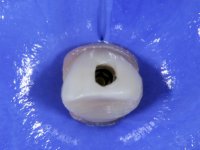

Before the treatment plan was elaborated, the patient was made aware of the inherent technical difficulty in aesthetical rehabilitation of the implant. After a long exchange of opinions with the dental technician, an unconventional treatment plan was presented, whose purpose was to minimize the aesthetic asymmetry between the left and right sides and between the cervical and incisal levels. The solution comprehended the realization of two veneers in composite resin of gingival tonality, to rehabilitate the interdental papillae of the edentulous space. A screwed abutment in Zr. with coronary and gingival component was planned for placement over the implant. As the implant angulation would put access to the screw on the vestibular face, confection of a feldspathic veneer was proposed, to be bonded to the abutment in order to camouflage the screw access hole. In tooth 1.2 a feldspathic veneer would be bonded, to correct microdontia and the small rotation.

An impression was made on the implant with open tray technique using soft and regular consistency putty. At the laboratory, after confection of the work model, a diagnostic waxing was performed, which sought to find an aesthetic compromise solution. In this sense, a temporary workpiece screwed onto the implant was used to simulate the difficulties we would have with screwing the definitive work. This study abutment consisted of wax to reproduce soft and hard tissues, seeking to anticipate the use of ceramics of gingival and coronary shade. Also, part of the interproximal papillae corresponding to the distal portion of the 2.1 tooth and the mesial tooth of the tooth 2.3 were also waxed, anticipating the use of composite resin “chips” with gingival tonality. Finally, a veneer was waxed to correct the microdontia of the tooth 1.2. In this waxing, the vestibular emergence of the orifice for access to the screw of the implant abutment was evident. Once this therapeutic option was accepted, the implant abutment in polymerized composite resin was prepared at the lab, as well as the papillary "chips", also in composite resin of gingival tonality. Tested in the mouth, the abutment was screwed and the "chips" bonded. The access hole of the screw was filled with composite resin. In subsequent consultation, a gingivectomy was performed on the cervical contour of teeth 1.3, 1.2 and 1.1 with the aim of correcting the asymmetry between the first and second quadrant. After the soft tissues were cicatrized, a dental bleaching was performed according to the patient’s aesthetic requirements. Final impression on the implant was made using the silicone open tray technique, taking care to individualize the transfer piece by copying the emergence profile of the patient’s provisional abutment. At the laboratory, the impression yielded a definitive working model, on which the abutment was waxed on a plastic insert. This process was carried out with the orientation of a wall of silicone based on diagnostic waxing. The wax made on the plastic part was placed in a special holder that allowed its scanning in a laboratory scanner. This scan by CAD process informed the design of an abutment in Zr. later materialized by a CAM process. The Zr. abutment was tested in the mouth, validating its clinical and imaging establishment. During this consultation, the choice of color was made by the ceramist, of both the coronary ceramics and the ceramic of gingival tonality to be used. Individualized color scales were used. At the laboratory, the coronary and gingival ceramics were placed on the implant abutment and later, on a working model with refractory gypsum, a veneer of feldspathic ceramic was made. This veneer was built on a surface specially designed for this purpose in the abutment. This surface tried to reproduce a dental preparation performed for the same effect. In the mouth the abutment was screwed with a torque of 35N, the access hole to the screw was filled with Teflon and later filled with composite resin. The veneer was bonded onto the implant abutment using the conventional bonding technique, with relative insulation. For economic reasons, the patient did not proceed to perform the veneer on tooth 1.2. Although a limited aesthetic compromise was expected from the outset, a result was achieved which satisfied the patient.